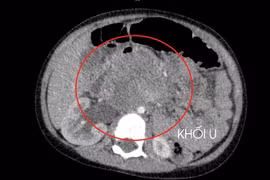

Phát hiện ung thư tinh hoàn nhờ dấu hiệu không ngờ này

Tinh hoàn phải nam thanh niên to dần kèm đau nhức suốt 2 tháng, khi đi khám, bác sĩ phát hiện bị ung thư tinh hoàn.